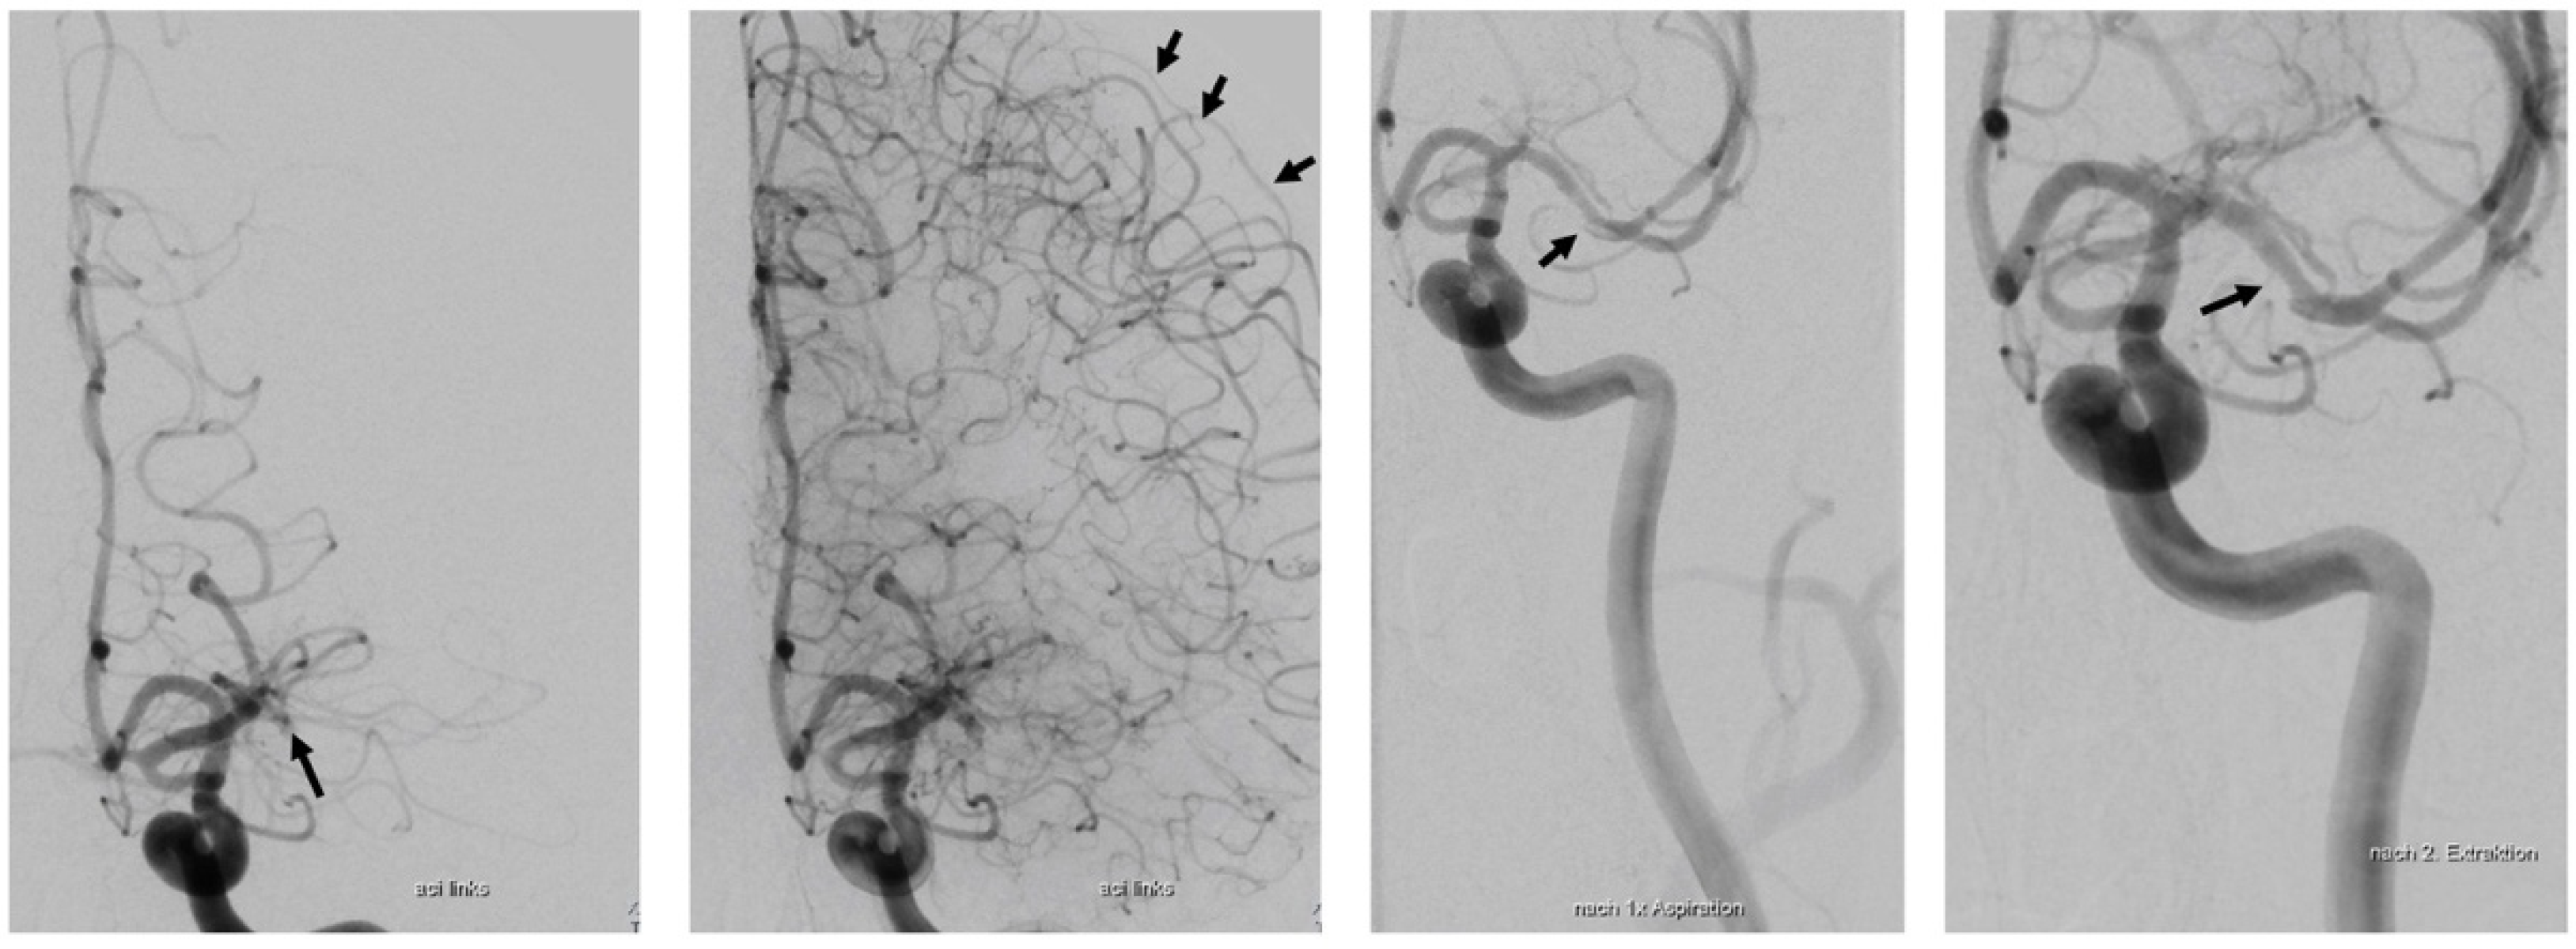

Case Report Continued